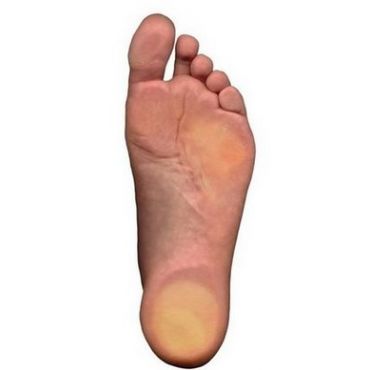

Your feet are the foundation of your body.

When you are experiencing problems with or pain in your feet, it affects your well being. These problems can make it difficult to manage all aspects of your life in a healthy and productive way. Seeing a podiatrist could be the right answer.

Our podiatrists are here to help you build a strong and healthy foundation by addressing any podiatric issues that may be keeping you from your best self.